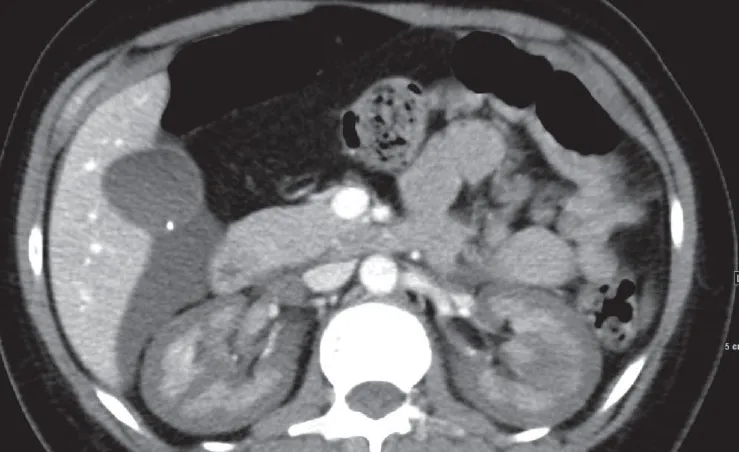

IRA + Icterícia: Um Caso que Exige Investigação Detalhada